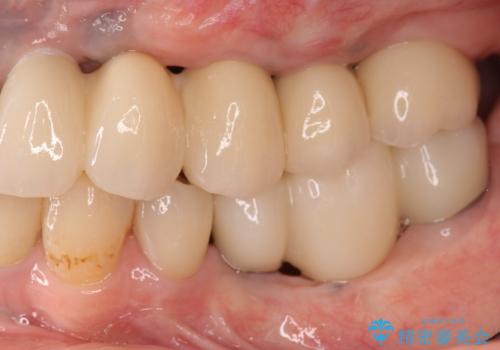

工程数が多かったため治療期間はかかりましたが、しっかりと安定した噛み合わせ、審美的な口腔内環境を達成することができ大変満足していただくことができました。